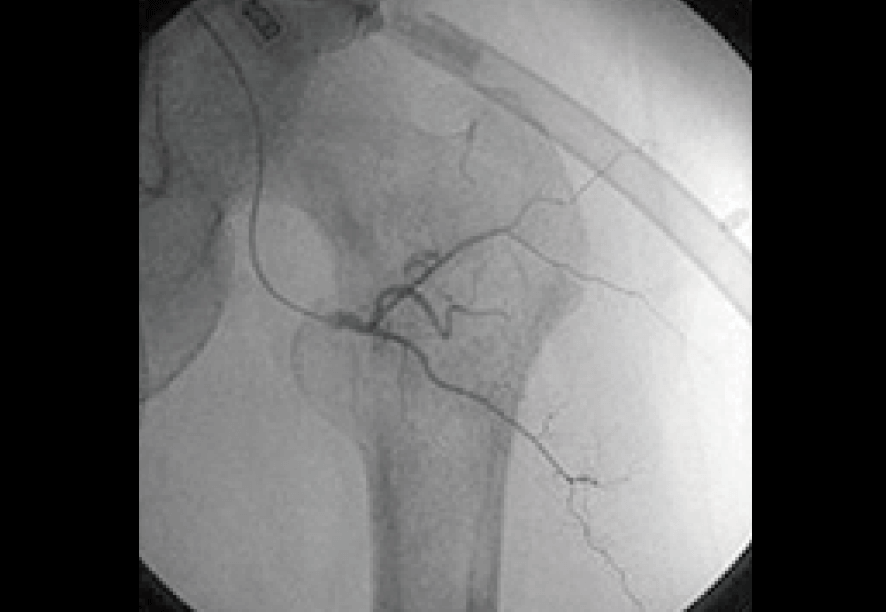

治療が一段落した後の調査画像。

治療前に大量に存在したがんの新生血管はほとんど消失。

治療はおよそ約4ヶ月間、外来通院と入院によって行われ、その結果著しい痛みを伴う症状はおよそ1カ月で改善。

その後にがん活動性は治療開始3ヶ月で低下傾向を見せ始め、急速な縮小を認めた。